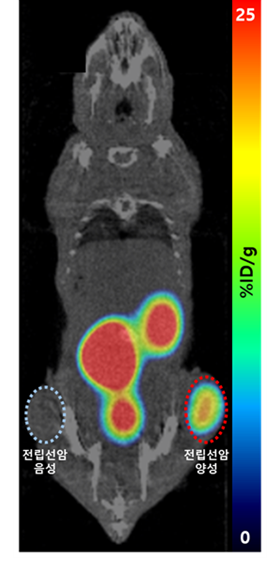

연구팀은 개발한 소재로 만든 용출한 갈륨-68을 이용해 분당서울대병원 핵의학과와 공동으로 전립선암 진단용 방사성의약품 비임상 실험을 수행해 유효성을 검증했다.